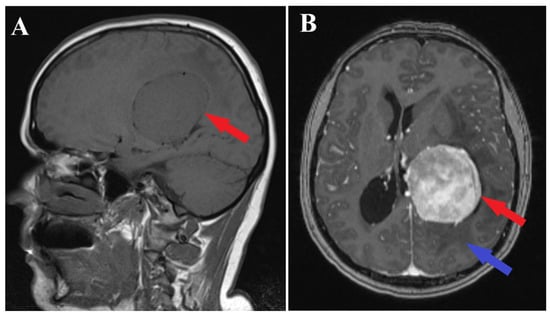

A brain MRI (i.e., multi-planar, multi-sequential brain MRI examination was performed on a General Electric 3T Signa Architect, Chicago, IL, USA) with contrast enhancement revealed an intraventricular tumor located in the body of the left lateral ventricle. The tumor presented as an ovoid, well-delineated mass with T1 hypointensity and T2 hyperintensity, measuring up to 60 mm in maximum diameter. It induced deformation of the left lateral ventricle. The tumor was associated with substantial digitiform edema, causing a shift in the midline structures and a potential risk of subfalcine herniation (Figure 1 and Figure 2).

Figure 1.

Preoperative MRI T1 and T1Gd sequence. Sagittal section of MRI T1 sequence (A) and axial section of MRI T1 Gd sequence (B), depicts an intraventricular mass into the left ventricle body (red arrows) with associated perilesional edema (blue arrow).